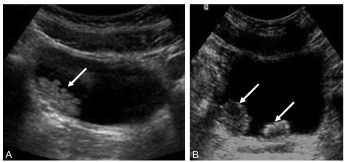

En échographie (figure 33.1), c’est une masse échogène à protrusion intraluminale, à contours internes réguliers ou non, sessile ou pédiculée, fixée sur la paroi vésicale. Une vascularisation est parfois visible en mode doppler.

Fig. 33.1 Échographie par voie sus-pubienne (vessie pleine).

Tumeur vésicale unique (A) : masse pariétale unique à bord interne frangé (flèche) de la corne vésicale droite. Tumeur vésicale multifocale (B, flèches) : présence de plusieurs masses polypoïdes.

Source : CERF, CNEBMN, 2022.

Le diagnostic différentiel consiste en des caillots parfois associés (mobiles et non vascularisés en doppler).